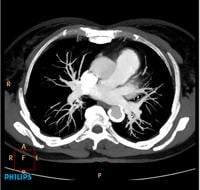

A low-dose neuro CTA using a Philips Ingenuity CT.

Computed tomography angiography (CTA) is one of the most complex procedures routinely performed on a CT scanner. A successful CTA exam requires synchronization of the timing of the scan with maximum vessel contrast enhancement.

With its patient focus and clinical integration, Philips Ingenuity CT provides the necessary tools and dedicated workflow to perform a successful CTA exam time after time. Following are some of the features: